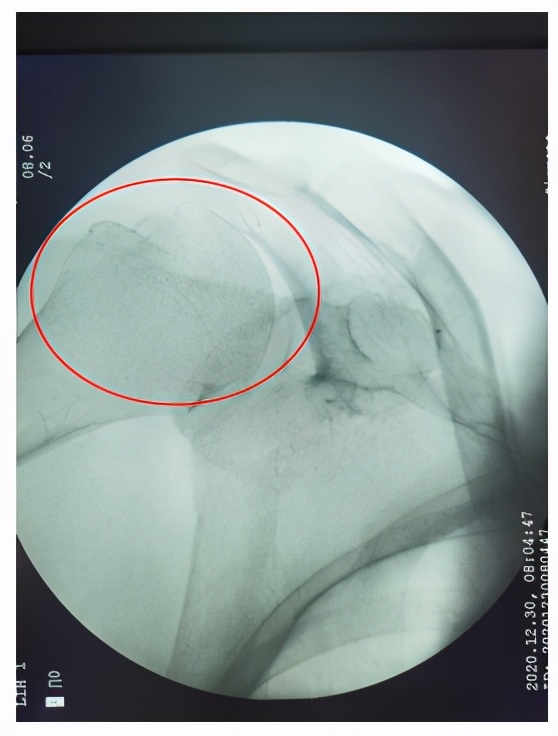

手法复位后X光片

那么一旦发生肩关节脱位后应该怎么办呢?吴向阳副主任医师指出,发生脱位后应尽快就医进行复位,复位分为手法复位和手术复位,一般前脱位常采取手法复位,但复位前需排除骨折,应尽早、轻柔复位,并采取多种措施减轻患者的疼痛;复位成功后要固定,佩戴前臂吊带3-4周。